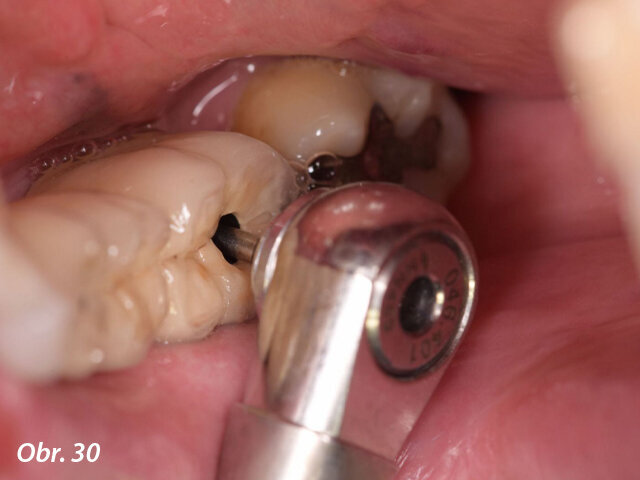

Kromě toho byla ve vestibulární oblasti implantátu v oblasti zubu 34 současně provedena augmentace za použití membrány Straumann Jason a kostního štěpu. Důvodem této horizontální augmentace byla tenká (méně než 1,5 mm) zbytková kost ve vestibulární oblasti (obr. 15). Kolagenní membrána byla stabilizována pomocí zirkonového vhojovacího abutmentu (RC ø 4,5 mm, výška 4 mm), zatímco pro implantát v oblasti zubu 36 byl našroubován titanový vhojovací abutment (RC ø 4,5 mm, výška 4 mm). Laloky byly uzavřeny umístěním jednoduchých stehů Vicryl 5/0 (obr. 16–20).